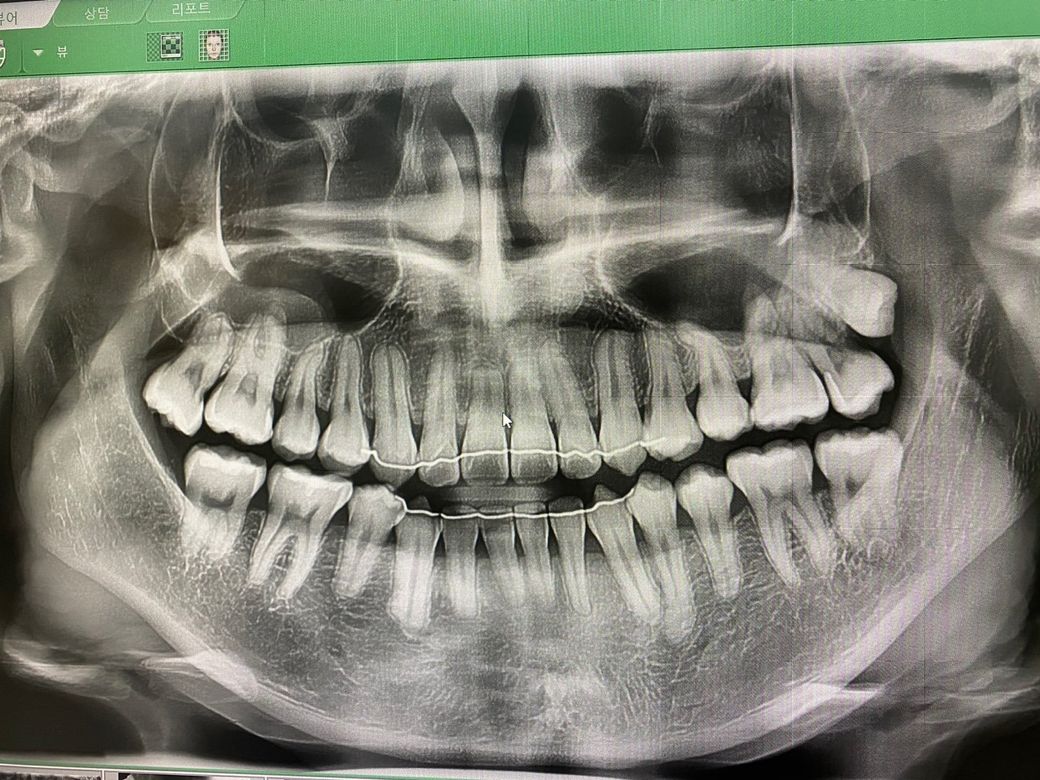

2차원적인 파노라마 영상만으로는 전체 치열을 판단할 수 없으며, 재교정이 필요한지 여부는 파노라마 사진 뿐만 아니라 실제 구강내 상태 등 여러 정보를 종합적으로 보고 판단할 수 있습니다.

다만 오른쪽 끝 어금니에는 옆면에 충치가 발생한 것으로 보이며, 신경치료나 발치가 필요한 상황으로 보입니다.

우선 교정치과에 내원하여 치열에 대한 평가가 먼저 이뤄진 뒤, 발치여부를 판단하는 것이 좋을 것으로 보입니다.

일단 위쪽 어금니에 신경치료를 시도해볼 수 있어 보이나 예후가 좋지 않아 보입니다. 발치할 가능성이 매우 커 보이며 이때 사랑니까지 발치해야할 가능성이 큽니다. 따라서 신경치료보다는 발치를 하는 것이 좋아 보입니다. 현재 보이는 정도로는 재교정을 할 수는 있으나 교정이라는 것은 환자분의 요구사항과 가능한 정도를 정확히 알고 시작하는 것이 필요합니다.

따라서 사랑니와 위어금니를 발치하고 교정과 선생님과 상담이 필요해보입니다.